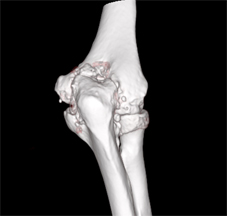

主要用來治療輕度到中度肘關節炎,同時此術式結合肘關節鏡的方式治療(如;圖二),只需要兩個小傷口就可達到切除骨刺、移除碎骨等,且有減輕疼痛的效果。只是相對於嚴重的肘關節炎來說,單用此術式就很難有效增進關節活動程度,所以必須以開放性Outerbridge-Kashiwagi術式治療(如:圖三),就可達到較佳的關節活動度。

圖二、關節鏡Outerbridge-Kashiwagi手術,從後側的入口在鷹嘴突凹窩鑿出一個窗口,可以移除前方關節腔的碎骨